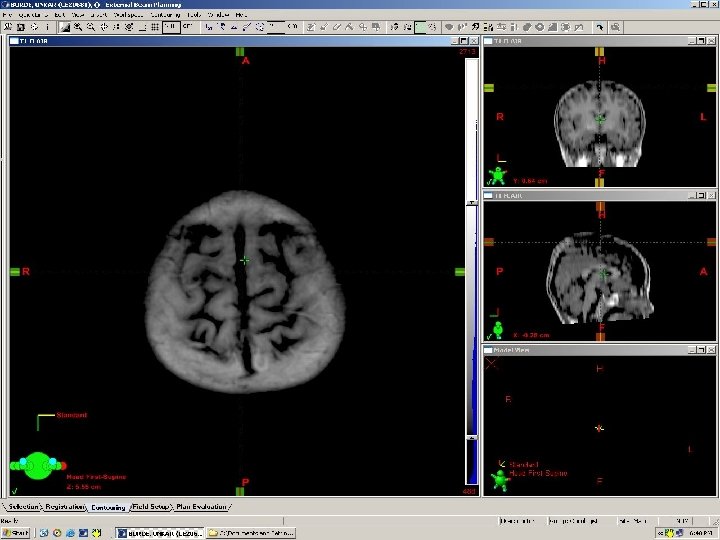

Three-Dimensional Fast Spoiled Gradient-Recalled (3 D-SPGR) magnetic resonance imaging (MRI) Standard 1. 5 Tesla MRI Modified T 1 Post Contrast Contiguous Sections 2 mm – 1 mm thickness 256 x 256 grid